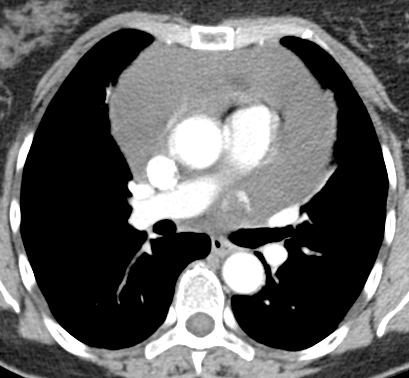

Cardiothoracic surgery was contacted for a pericardial window and biopsy. A repeat contrast enhanced chest CT scan suggested an 18 x 16 mm peripherally enhancing intrapericardial mass, with central low attenuation between the main pulmonary artery and the left atrial appendage. The pericardial effusion was massive, the pericardium was mildly thickened, and a right apical 3 mm pulmonary nodule was evident (Fig. 3).